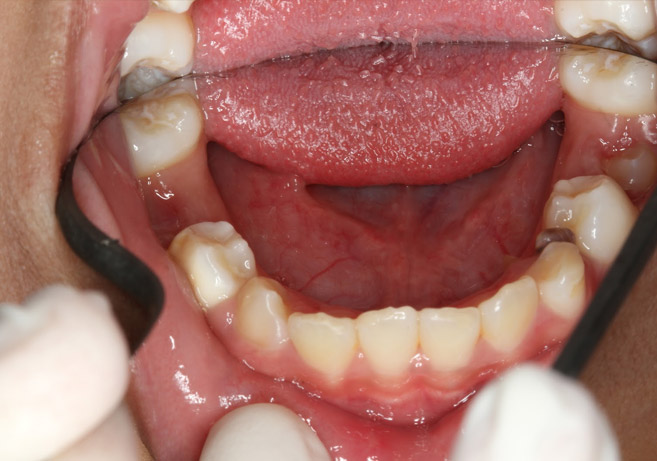

Carious Lesions: 55OL, 54O/retained root, 64O, 65OL, 75O, 34BO, 83 retained root, 85O

Intra-Oral Photos at Initial Examination